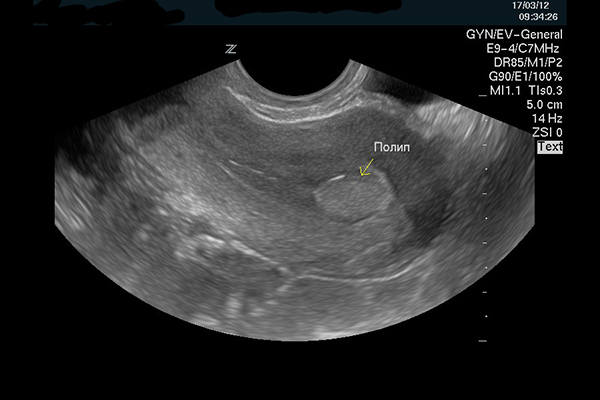

На фото ниже показано изображение УЗИ полипа в матке.

На УЗИ полип характерен некоторыми особенностями:

- округлой формой ;

- четкими контурами;

- расширением шеечного канала и полости матки;

- умеренной деформацией срединно-поперечной части М-эхо;

- наличие кист эндометрии рядом с основанием ножки образования.

Как выглядит полип в матке на УЗИ?

Полип матки на УЗИ выглядит как новообразование с четким контуром. Другим его признаком может стать расширение полости и утолщение стенки матки. Для диагностики новообразований лучше всего подходят 5-7 дни менструального цикла.